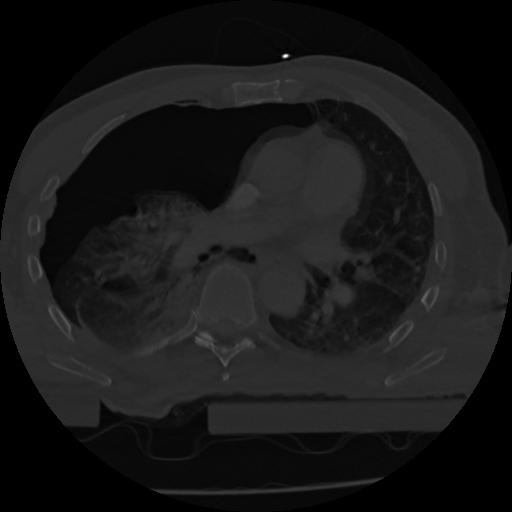

22 ANGIO,CE,Vol,0.5,ANGIO,,